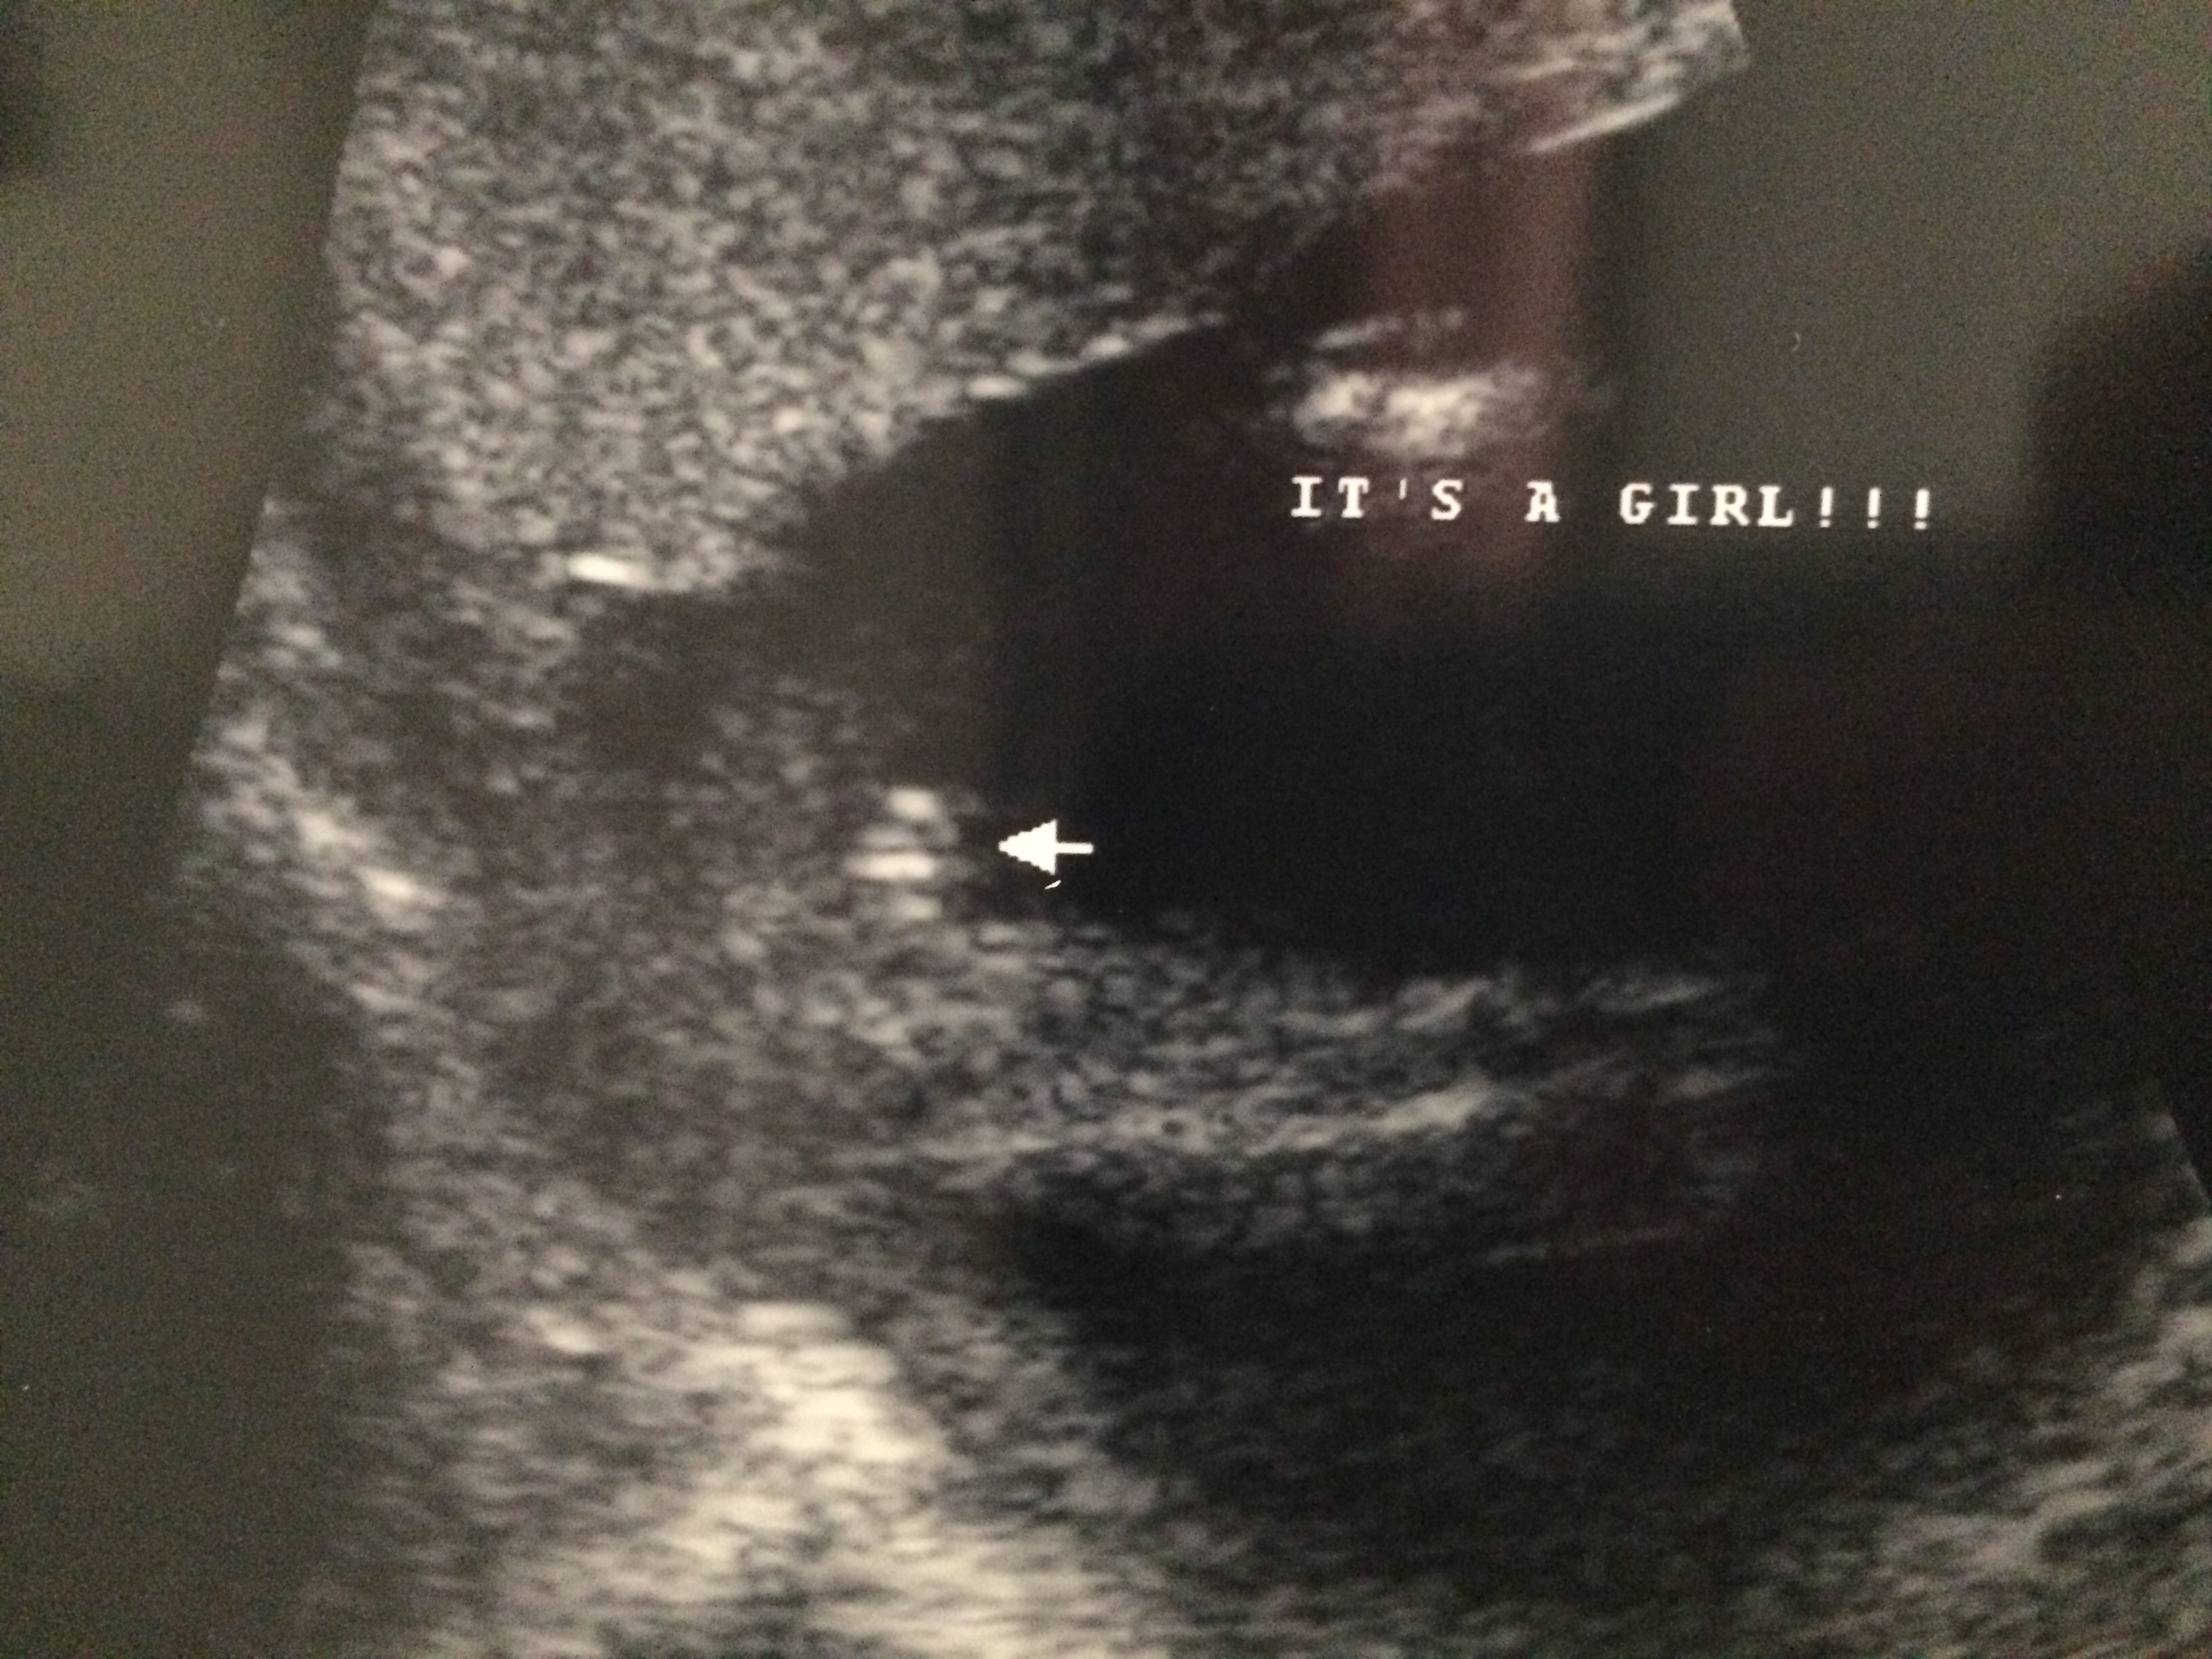

We got a private scan at 16 weeks 5 days. The ultrasound tech said she was 100% sure it was a girl. But for some reason I'm still freaking myself out. His mom has bought so many girl clothes already ( first grandchild ) I'm now 21 weeks and I go in 2 days for my anotomy / growth scan, which I know they don't really focus that much on gender like they would with a private scan. I would just like some other mommies opinions for comfort!!! ☺️ thanks !

• Looks like a girl! Congrats!

• Congrats!! It looks like a girl to me.

• I'm an X-ray tech not ultrasound but that looks like a girl to me!

• Girl.